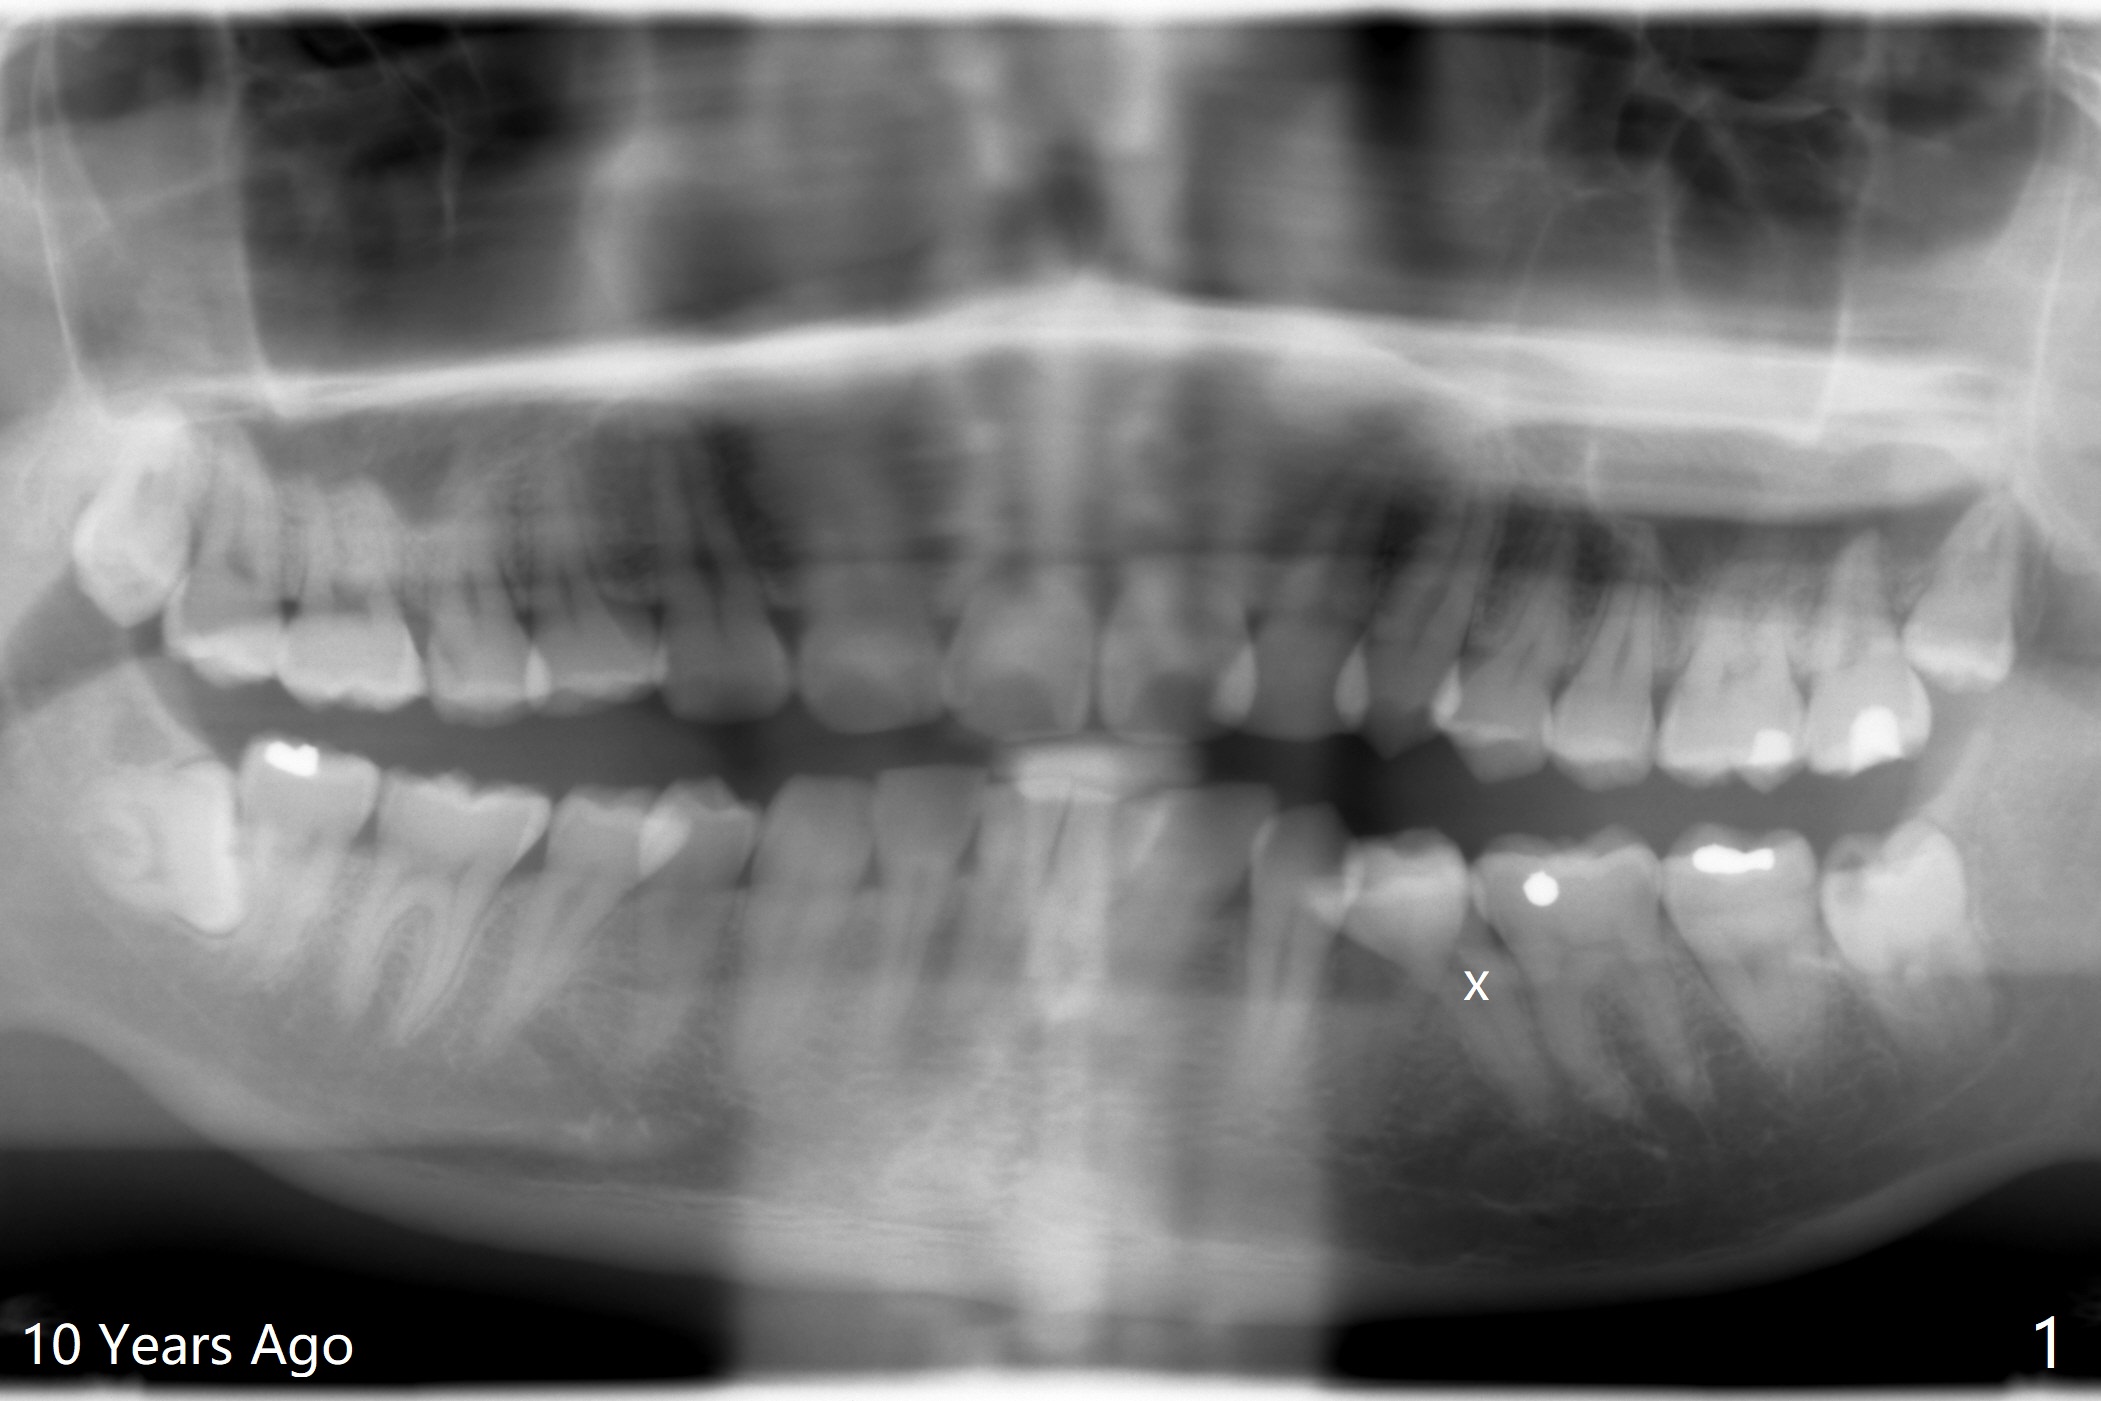

A 32-year-old man has had severe crowding for the last 10 years (Fig.1-5).  He is ready for orthodontic treatment now.  LL5 has been extracted for 4 years (Fig.1 x).  Severe caries at UR5 makes it easy to decide for extraction (Fig.2 x), while it is hard to determine which of the LR bicuspids needs to be extracted because of moderate caries at LR5 and even harder for UL because of caries at UL6,7 (Fig.2 *).

In fact impression for models (Fig.3-7) is taken after UL caries control.  Sedative filling is done at UL1,3 (Fig.6 *) and definitive restoration will be done when crowding resolves.  The defects at UL6,7 (Fig.6 x) is so extensive that after composite molar bands are placed immediately for retention.  Amazingly, there is no symptom after UL6,7 restoration.  Therefore UL4 will be extracted for crowding resolution.  UR 5 (Fig.1-3,6) has been extracted, while LR5 (Fig.2,7) will be.